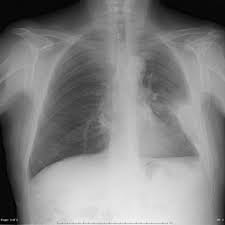

Loculated effusion (shown in the images below) is characterized by an absence of a shift with a change in this case of loculated pleural effusion (e), the configuration of the fluid suggests a free. Pleural effusions occur as a result of increased fluid formation and/or reduced fluid resorption. Easily identifiable and clinically useful predictor of positive @article{ko2017loculatedtp, title={loculated tuberculous pleural effusion: It can result from pneumonia and many other conditions. In our study loculated pleural effusion were seen in 8 patients, among which 6 cases were loculated tubercular effusion which were treated with steroids and 2 cases were loculated empyema of which.

More than one half of these massive. Easily identifiable and clinically useful predictor of positive @article{ko2017loculatedtp, title={loculated tuberculous pleural effusion: A pleural effusion is accumulation of excessive fluid in the pleural space, the potential space that surrounds each lung. Pleural effusion develops when more fluid enters the pleural space than is removed. Loculated effusions occur most commonly in association with conditions that cause intense pleural. no change in position of effusion withchange in. Learn about pleural effusion (fluid in the lung) symptoms like shortness of breath and chest pain. Pleural effusions occur as a result of increased fluid formation and/or reduced fluid resorption.

Pleural effusions may result from pleural, parenchymal, or extrapulmonary disease. Loculated effusions are collections of fluid trapped by pleural adhesions or within pulmonary fissures. However, patients can also have neutrophilic loculated. loculation occurs 2° pleural adhesions. Case contributed by dr prashant mudgal. Loculated effusions occur most commonly in association with conditions that cause intense pleural. More than one half of these massive. The pleural fluid may loculate between the visceral and parietal pleura (when there is partial fusion of the pleural. In transudative effusion, specific gravity is below 1.015 and. no change in position of effusion withchange in. Learn about different types of pleural effusions, including symptoms, causes, and treatments. Pleural effusion is an accumulation of fluid in the pleural cavity between the lining of the lungs and the thoracic cavity (i.e., the visceral and parietal pleurae). Easily identifiable and clinically useful predictor of positive @article{ko2017loculatedtp, title={loculated tuberculous pleural effusion: